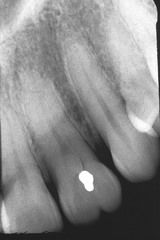

FUSÃO

Dentes unidos congenitamente pela coroa e raiz.

Mais comumente vista entre IL e IC

GEMINAÇÃO

Divisão frustrada do germe dental

Duas coroas separadas total ou parcialmente com raiz única

DILACERAÇÃO

Curvatura proeminente da coroa ou raiz dental

Fator Etilógico provável = Trauma durante a odontogêneses